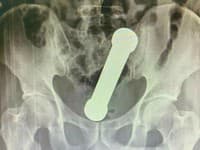

Keď si Patrick Howard v apríli 2020 všimol svrbenie a začervenanie na svojom penise, myslel si, že ide o bežnú kvasinkovú infekciu. Diagnóza, ktorá nasledovala v októbri, ho však šokovala – lekári mu oznámili „agresívnu“ formu penilného karcinómu spôsobeného vírusom HPV a označili ju za smrteľnú.

Prišiel o dve tretiny pohlavného údu

Patrick, 65-ročný dôchodca z Liverpoolu, mal byť podľa lekárov „hotový“ do roka, informuje britský magazín The Sun. Operácia, ktorá nasledovala, znamenala odstránenie približne dvoch tretín penisu a viaceré ďalšie zákroky, vrátane odstránenia lymfatických uzlín a následnej radioterapie a dvoch typov chemoterapie. Napriek všetkým predpokladom a „brutálnej“ liečbe sa Patrick dožil viac než dvojročnej doby bez ďalšej liečby. Lekári ho označili ako „prekračujúceho očakávania“ a kontrolné vyšetrenia ukazujú, že sa choroba ďalej nešíri.